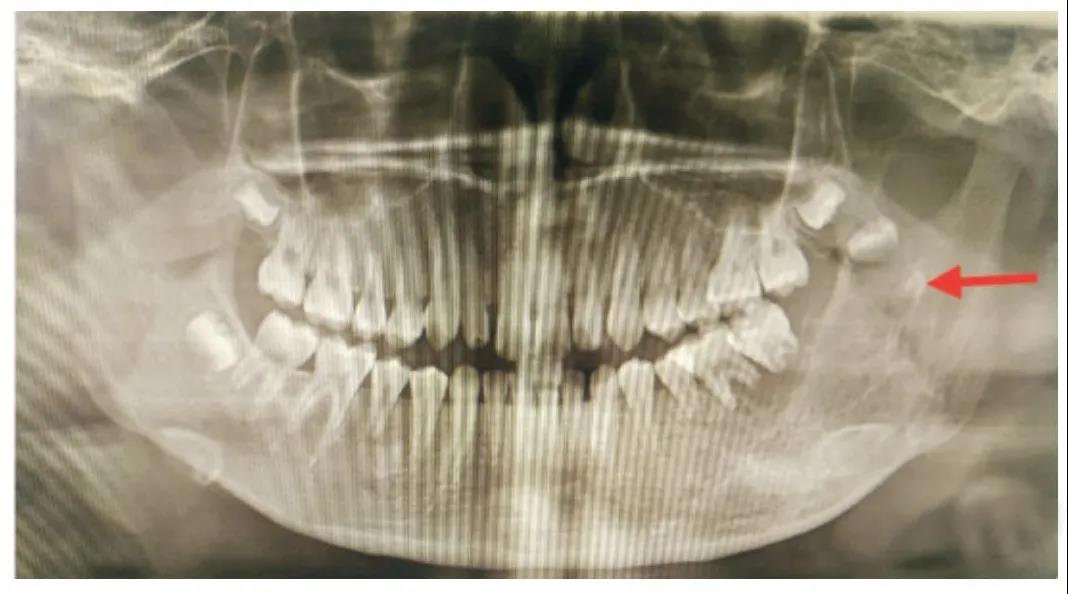

8、除了第3磨牙与多生牙,一般成人拔牙后均需安装假牙,大约拔牙后3个月左右应修复,以避免邻牙倒伏,从而在牙列中引发多米诺骨牌效应!